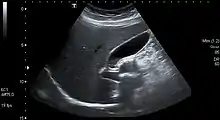

Abdominal ultrasonography showing gallbladder and common bile duct

The gallbladder varies in size, shape, and position among different people.[2] Rarely, two or even three gallbladders may coexist, either as separate bladders draining into the cystic duct, or sharing a common branch that drains into the cystic duct. Additionally, the gallbladder may fail to form at all. Gallbladders with two lobes separated by a septum may also exist. These abnormalities are not likely to affect function and are generally asymptomatic.[8]